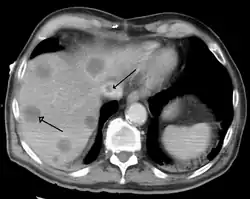

Una hepatopatía previa no diagnosticada se puede detectar tras la autopsia. Abajo se muestran imágenes de la patología:

-

Cirrosis difusa -

Cirrosis macronodular -

Textura de nuez moscada de la hepatopatía congestiva -

Metástasis hepáticas